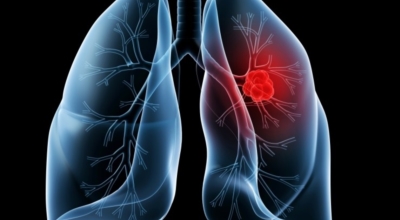

폐암 치료방법

폐암 검사는 X-ray를 통해서 검사하는데 , 크기가 작거나 구석에 위치한 경우 확인이 어려운 경우도 있습니다. 그리고 조직 검사를 통해서 정확한 진단을 하게 되어요. 폐암이 발견되면 종양의 크기나 전이 여부 , 위치에 따라서 수술 여부를 결정하게 돼요.

수술 치료

악성 종양이 있는 폐의 일부를 절제하는 방법입니다. 초기에는 내시경 기구를 활용하여 수술이 가능하기도 해요.